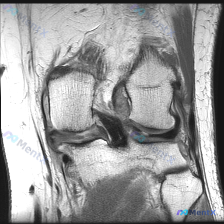

看到一份膝关节MRI的影像资料,问题是观察半月板异常,整理一下完整分析思路分享给大家。 病例基本影像信息 这是一份膝关节冠状位T1加权MRI的单影像分析,核心异常聚焦在半月板: 1. 骨骼结构:股骨远端、胫骨近端骨质信号均匀,无骨髓水肿、骨质破坏,皮质连续完整 2. 关节软骨:关节面软骨形态规整,无...